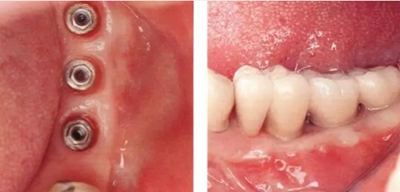

▲圖10-1,2

圖10-1 頰側和牙槽嵴有角化齦的存在,但是愈合期間內覆蓋螺絲露出(Type3-Class2)